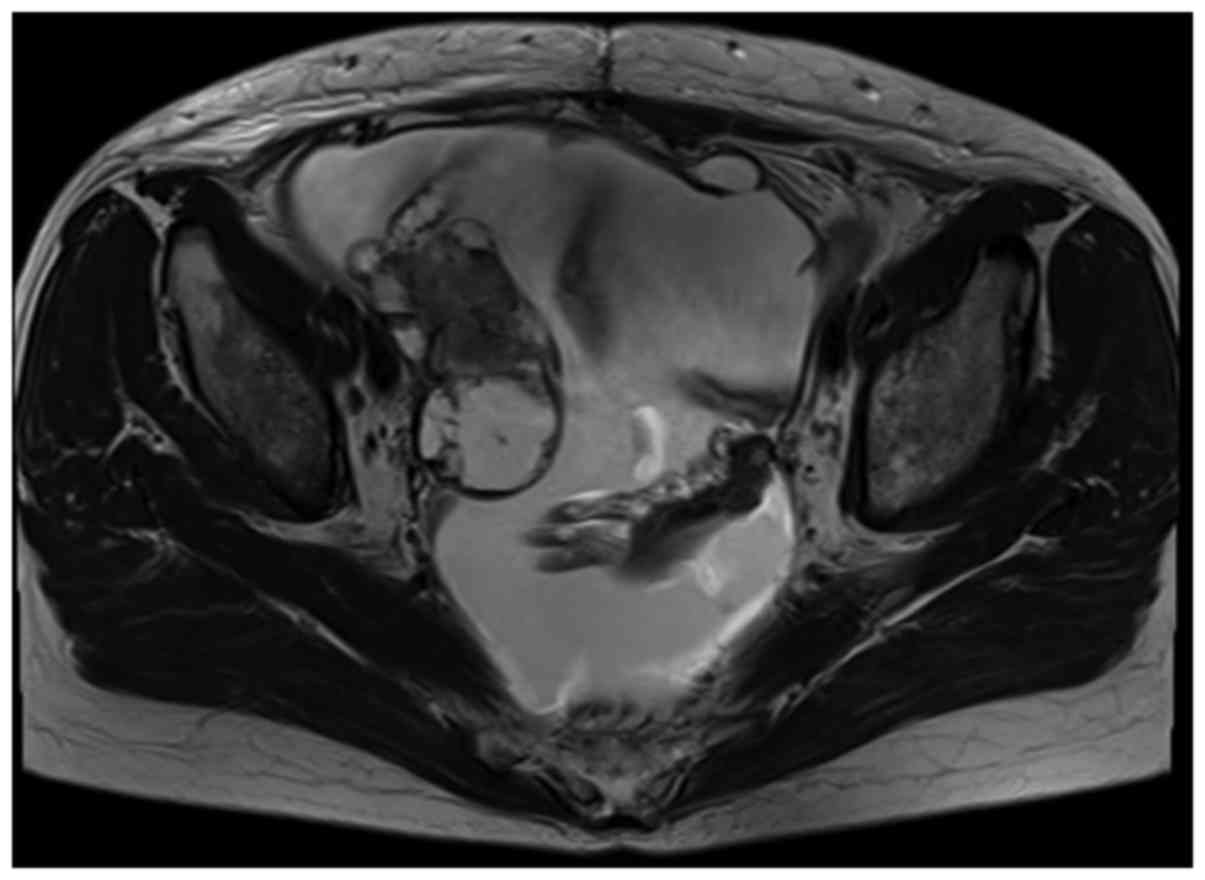

High-grade serous ovarian cancer 3 years after bilateral salpingectomy: A case report

Although epithelial ovarian cancer commonly originates from the ovarian surface epithelium and/or ovarian inclusion cysts, it was recently proposed that high‑grade serous ovarian cancer (HGSC) develops from the fallopian tubes. In our department, we encountered a case of HGSC that contradicts the hypothesis of a tubal origin for HGSC. A 51-year-old postmenopausal woman had undergone hysterectomy, left oophorectomy and bilateral salpingectomy for uterine myoma. Three years later, the patient was diagnosed with stage IV ovarian cancer and underwent primary debulking surgery. The pathological examination revealed HGSC, although there was no evidence of serous tubal intraepithelial carcinoma or any other type of cancer in the previously resected left ovary and bilateral fallopian tubes. Moreover, p53 overexpression was not detected in the right ovarian cancer specimen, while paired box gene 8, a marker of fallopian tube epithelium, was highly expressed. Therefore, HGSC may develop from an inclusion cyst with metaplasia of from the ovarian surface epithelium.

Figure 1

Figure 2

Figure 3